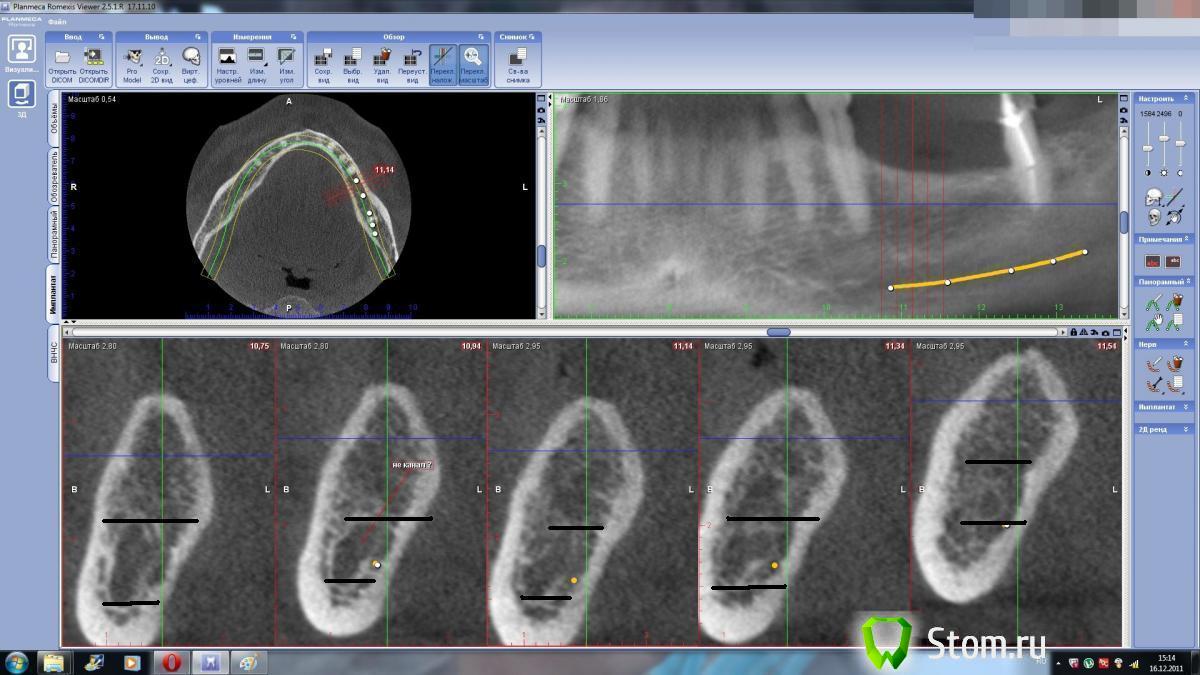

dent-a Опубликовано 16 декабря, 2011 Поделиться Опубликовано 16 декабря, 2011 Есть ли критерии hu для нижнечелюстного канала. Что то сомневаюсь по КТшке где канал и как следствие- расстояние до него. Может есть у кого светлые мысли или опыт.спасибо. Ссылка на комментарий

Bier Опубликовано 16 декабря, 2011 Поделиться Опубликовано 16 декабря, 2011 а в чем проблема? пятно то темное хорошо просматривается Ссылка на комментарий

merson Опубликовано 16 декабря, 2011 Поделиться Опубликовано 16 декабря, 2011 очень хорошо видно -Bier прав -темное пятно на срезах неправильной формы ближе к основанию челюсти Ссылка на комментарий

dent-a Опубликовано 16 декабря, 2011 Автор Поделиться Опубликовано 16 декабря, 2011 а в чем проблема? пятно то темное хорошо просматриваетсяЭм....может я туплю, но сможете в пэйнте - пометить верх и низ канала на вертикальных срезах.Я что то не могу определиться с глубиной формирования ложа.Спасибо. Ссылка на комментарий

kriokov Опубликовано 16 декабря, 2011 Поделиться Опубликовано 16 декабря, 2011 Для меня тоже проблема. Я так увидел. Ссылка на комментарий

dent-a Опубликовано 16 декабря, 2011 Автор Поделиться Опубликовано 16 декабря, 2011 Для меня тоже проблема. Я так увидел.Я так же разглядел (при таком положении канал уходит выше "проекции канала" на панорамных срезах на пару мм.).Человек в возрасте, адентия не первый день, есть склероз канала. Ссылка на комментарий